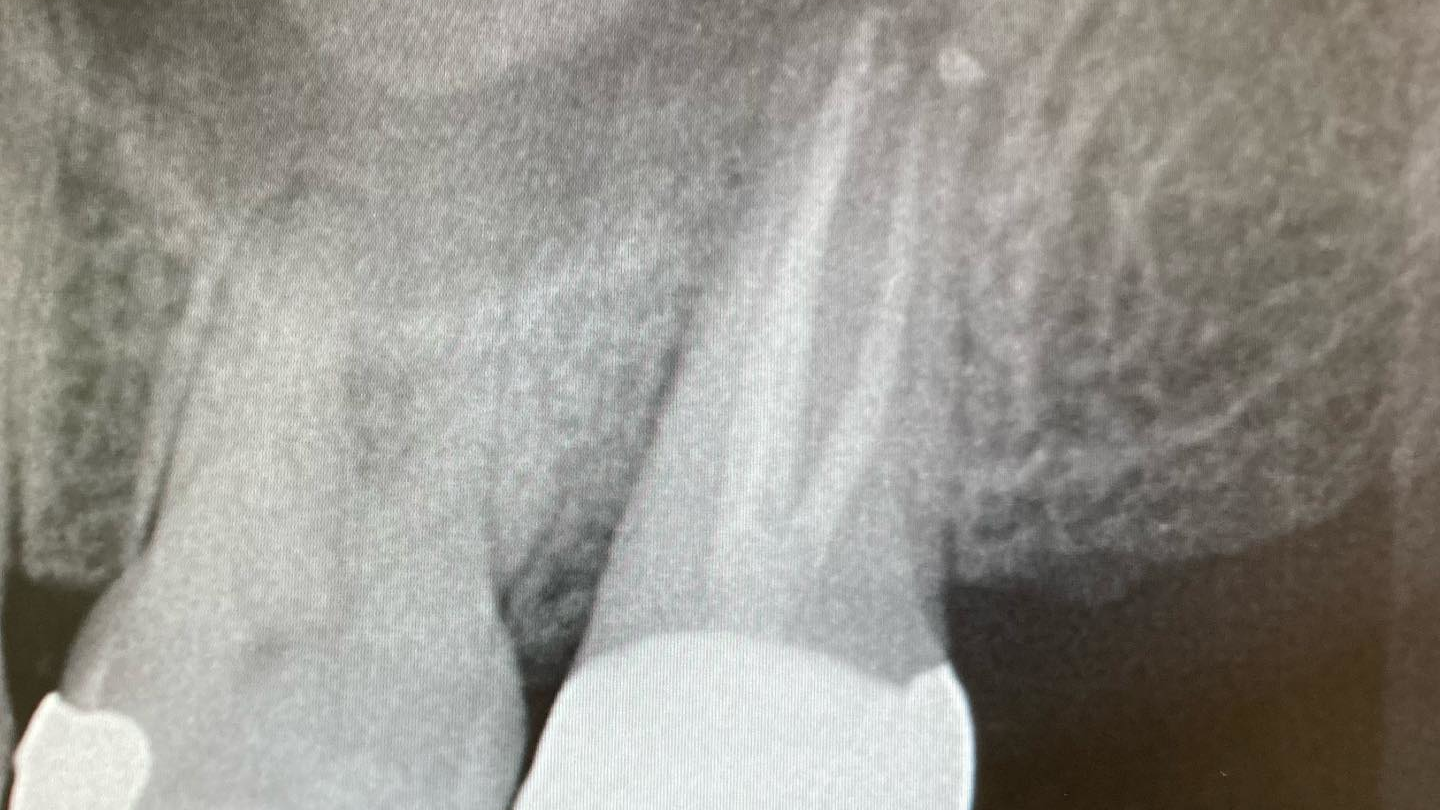

No. 3: Evaluate the radiographs.

Check the radiograph for a lateral defect (lucency) in the bone with little or no apical disease (figure 1). Cases where the disease shows bone loss lateral to the root, but the previous root canal treatment looks to have been filled to the apex, are likely fractures.

No. 4: Evaluate a cone beam CT scan.

If you can use a CBCT scan, it will give you more detail and can be helpful in discerning the pattern of bone loss, although it won’t necessarily show the root fracture itself. Failure of endodontic treatment commonly occurs at the portal of exit apically (unless there is a lateral canal midroot). Fractures are typically present with lateral bone loss (figure 2).